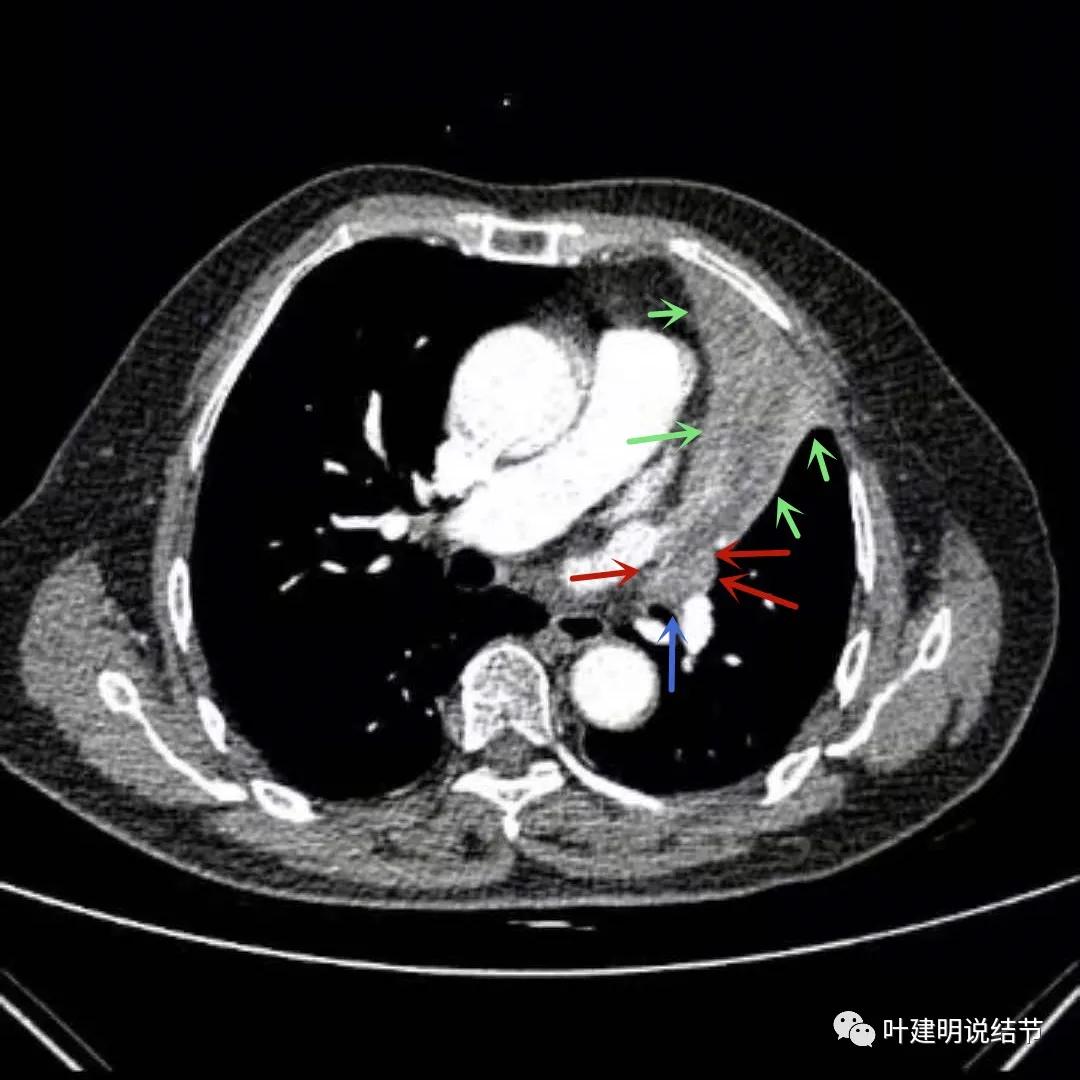

上图绿色箭头所指区域考虑为肺不张,红色示肿瘤处且有不均质与膨胀性,桔色粗箭头所指处是左侧肺动脉主干,桔色细箭头所示处是叶间动脉干。之所以肺动脉中间有软组织影,是因为肿瘤长到肺动脉与支气管之间的缝隙里,相当于血管是跨在肿瘤上,与肿瘤接触的这面是侵犯愈着的。粉色箭头示肿瘤累及左上叶支气管开口处,表面不平

上图绿色箭头所指区域考虑为肺不张,红色示肿瘤处,桔色箭头所指处分别是左侧肺动脉主干与叶间肺动脉。之所以肺动脉中间有软组织影,是因为肿瘤长到肺动脉与支气管之间的缝隙里。粉色箭头示肿瘤累及左上叶支气管开口处,表面不平;蓝色粗箭头示左下叶支气管开口,细的蓝色箭头示肿瘤与下叶支气管壁的外壁(上下叶开*交口**界处,或称汇总区)关系密切,疑有侵犯的可能

上图绿色箭头所指区域考虑为肺不张,红色示肿瘤处,桔色箭头所指处是叶间肺动脉。粉色箭头示肿瘤累及左上叶支气管开口处,表面不平;蓝色粗箭头示左下叶支气管开口